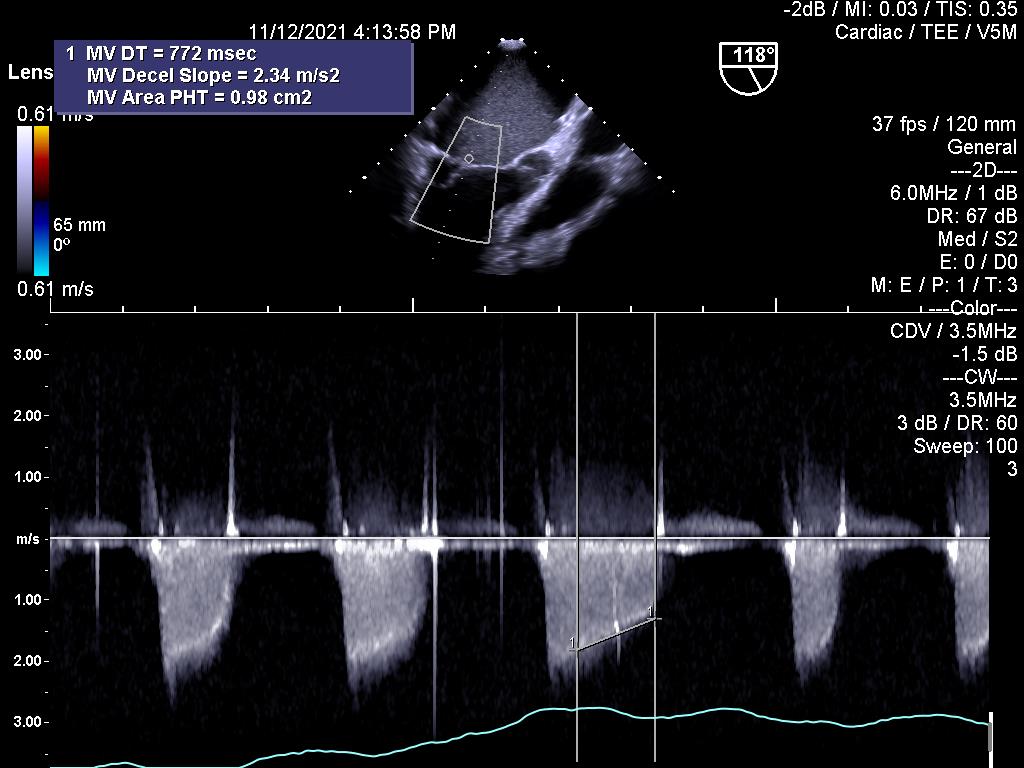

2.Đánh giá hiệu quả điều trị bằng thuốc tiêu sợi huyết đối với kẹt van cơ học (cùng bệnh nhân ở trên)